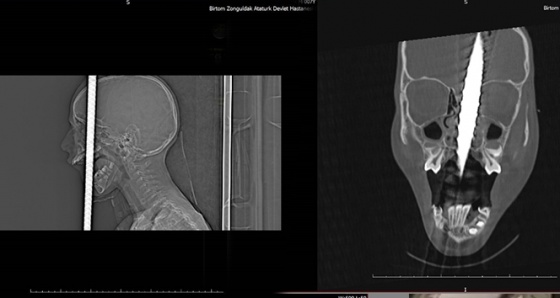

Zonguldak’ta kafasına demir saplanması sebebiyle Bülent Ecevit Üniversitesi Uygulama ve Araştırma Merkezine sevk edilen 7 yaşındaki Fırat Başaran’ın başındaki 1 metre uzunluğundaki demir çubuk, 6 saat süren operasyonla çıkartıldı.

Zonguldak’ta, bisikletiyle gezerken 2 metre yükseklikten düşen 7 yaşındaki Fırat Başaran’ın ağzından giren demir başından çıktı. Yaralı çocuk, ekipler tarafından Bülent Ecevit Üniversitesi Uygulama ve Araştırma Merkezine sevk edildi. Beyin cerrahisi, kulak burun boğaz, plastik cerrahisi, anestezi ve AFAD ekipleri başarılı bir ekip çalışması sonucunda 6 saat süren operasyonla 1 metre uzunluğundaki demir çubuk operasyonla alındı. Çocuk yoğun bakım ünitesine kaldırılan 7 yaşındaki Fırat Başaran’ın tedavisi devam ediyor. Bülent Ecevit Üniversitesi Sağlık Uygulama ve Araştırma Merkezi Müdürü Bekir Hakan Bakkal, ameliyata katılan 1 uzman doktor ve 6 öğretim üyesi ile birlikte 7 yaşındaki Fırat Başaran’ın ameliyatı ve sağlık durumu hakkında bilgiler verdi.

Doç. Dr. Bekir Hakan Bakkal, operasyonda emeği geçen tüm branştaki arkadaşlarına ve AFAD ekiplerine teşekkür etti. Hastanın 6 saat süren başarılı operasyonun ardından başında bulunan 1 metre uzunluğundaki demir çubuğun çıkartıldığını ifade eden Bakkal, “Atatürk Devlet Hastanesinden bize yönlendirilen 7 yaşındaki erkek çocuğumuz çok da rutin de görmediğimiz bir yaralanma ile acil servisimize başvurdu. Hastamız hastaneye başvurmadan önce hastamızla ilgili tıbbi bilgiler bize ulaştırıldığı için biz de ekip olarak beyin cerrahisi, kulak burun boğaz, anestezi, plastik cerrahi ve ameliyat ekibimiz hazır olarak bekliyorduk. Saat 18.00 gibi ameliyathaneye alındı. Üniversitemizdeki ilgili branş ekipleri ve Atatürk Devlet Hastanesinde beyin cerrahisi uzmanı operatör Dr. Emrah Keskin ile birlikte hasta ameliyata alındı. AFAD ekibi demirin kesilmesinde bizlere çok yardımcı oldu. İlk önce kulak burun boğaz tarafından hava yolu açıldıktan sonra AFAD ekipleri çıkarılacak olan çubuğun belli bir kısmını keserek yapılacak işlemde yardımcı oldu. Akabinde beyin cerrahisi gerekli işlemleri yaparak demir çubuğun çıkartılması konusunda rahat bir ortam hazırlamasını sağladı. Ardından çıkarılma işlemi tamamlandı. Ardından KBB ve plastik cerrahi oluşan defektle ilgili onarım işlemlerini tamamlandı. Hastamız şu an çocuk yoğun bakım ünitesinde bilinci açık bir şekilde takip edilmektedir. Burada tüm branştaki arkadaşlarımızın, ameliyat ekibimizin ve AFAD’ın çok büyük emekleri vardır. Ben hepsine hastanemiz adına teşekkür ediyorum” dedi.

İlk günlerin büyük önem taşıdığını ifade eden Beyin ve Sinir Cerrahisi Anabilim Dalı uzmanı Doç.Dr. Şanser Gül ise, “Hastamızı ilk olarak Atatürk Devlet Hastanesinde beyin cerrahisi uzmanı operatör Dr. Emrah Keskin görüyor ve durumu bize haber veriyor. Biz hazırlığımızı yaptık. Temel prensip ilk önce zarar vermeme, üst damaktan ağız içinden giren ve yaklaşık 1 metre uzunluğundaki demir çubuk kafatasını delerek sol ön fontelden 40 santim dışarı çıkmıştı. AFAD ekipleri tarafından 3 santim kalana kadar kesildi. Temel prensiplere bağlı kalarak parçalanan bölgeyi genişleterek demir çubuk rahatlatıldı. Sonra ameliyata alınarak demir çubuk çıkartıldı. Ön beyin düşünce davranışlarımızı yönlendirir; hafıza, düşünme, karar verme, idare etme gibi durumları evet çocuğumuz şu an yoğun bakımda bilinci açık bir şekilde zaman içinde neyi kaybettiğini görmüş olacağız. İlk günlerde hayati önem taşıyan bir durum var o da enfeksiyon ekip olarak tüm işlemler yapıldı. Antibiyotik tedavisine başlandı. İlerleyen günler her türlü sonuca açık” şeklinde konuştu.